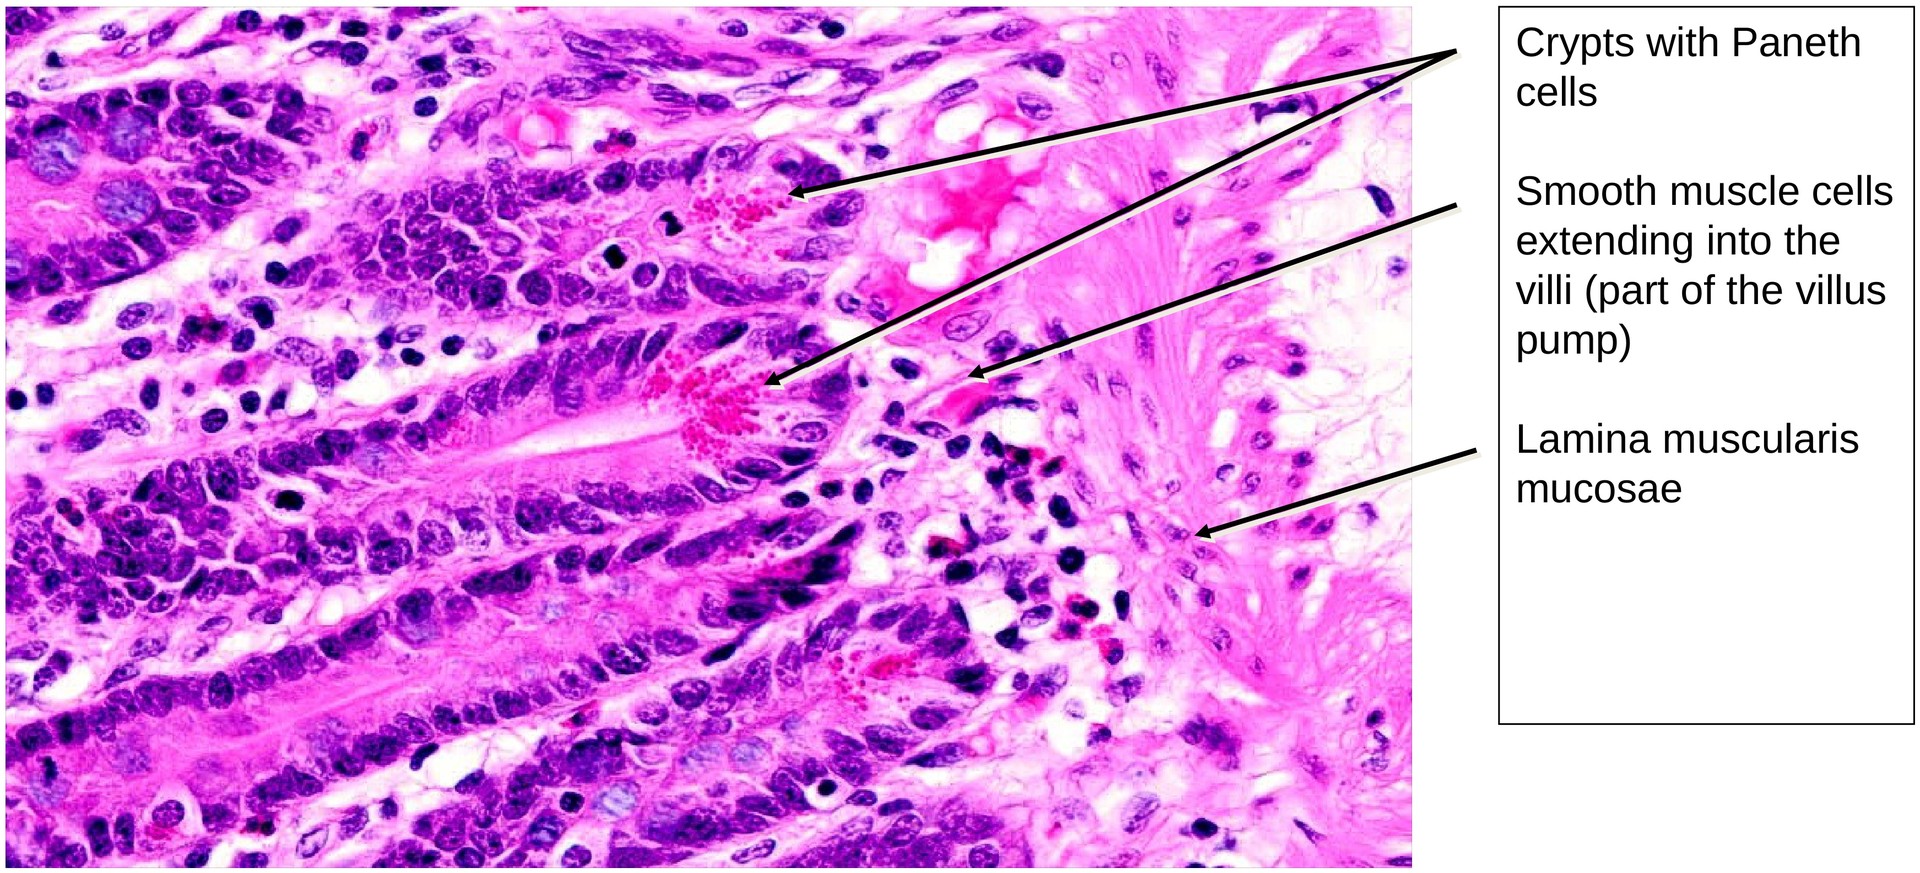

The lamina propria forms a relatively thin layer beneath the epithelium. The lamina muscularis mucosae is clearly developed; due to the tangential orientation of the section, it appears planar in several areas. Individual smooth muscle cells can be seen extending into the villi, forming the basis of the villus pump mechanism.

Within the crypts, Paneth cells are clearly visible; their apical granules are strongly eosinophilic, giving them a characteristic appearance in H&E staining.